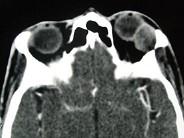

问题 女,36岁,左眼眶外上部可触及一无痛性包块有2年,眼球向内下方突出,CT检查如图,最可能诊断为()

选项 A.泪腺良性混合瘤 B.泪腺恶性上皮性肿瘤 C.炎性假瘤 D.淋巴瘤 E.淋巴瘤样增生

答案 A